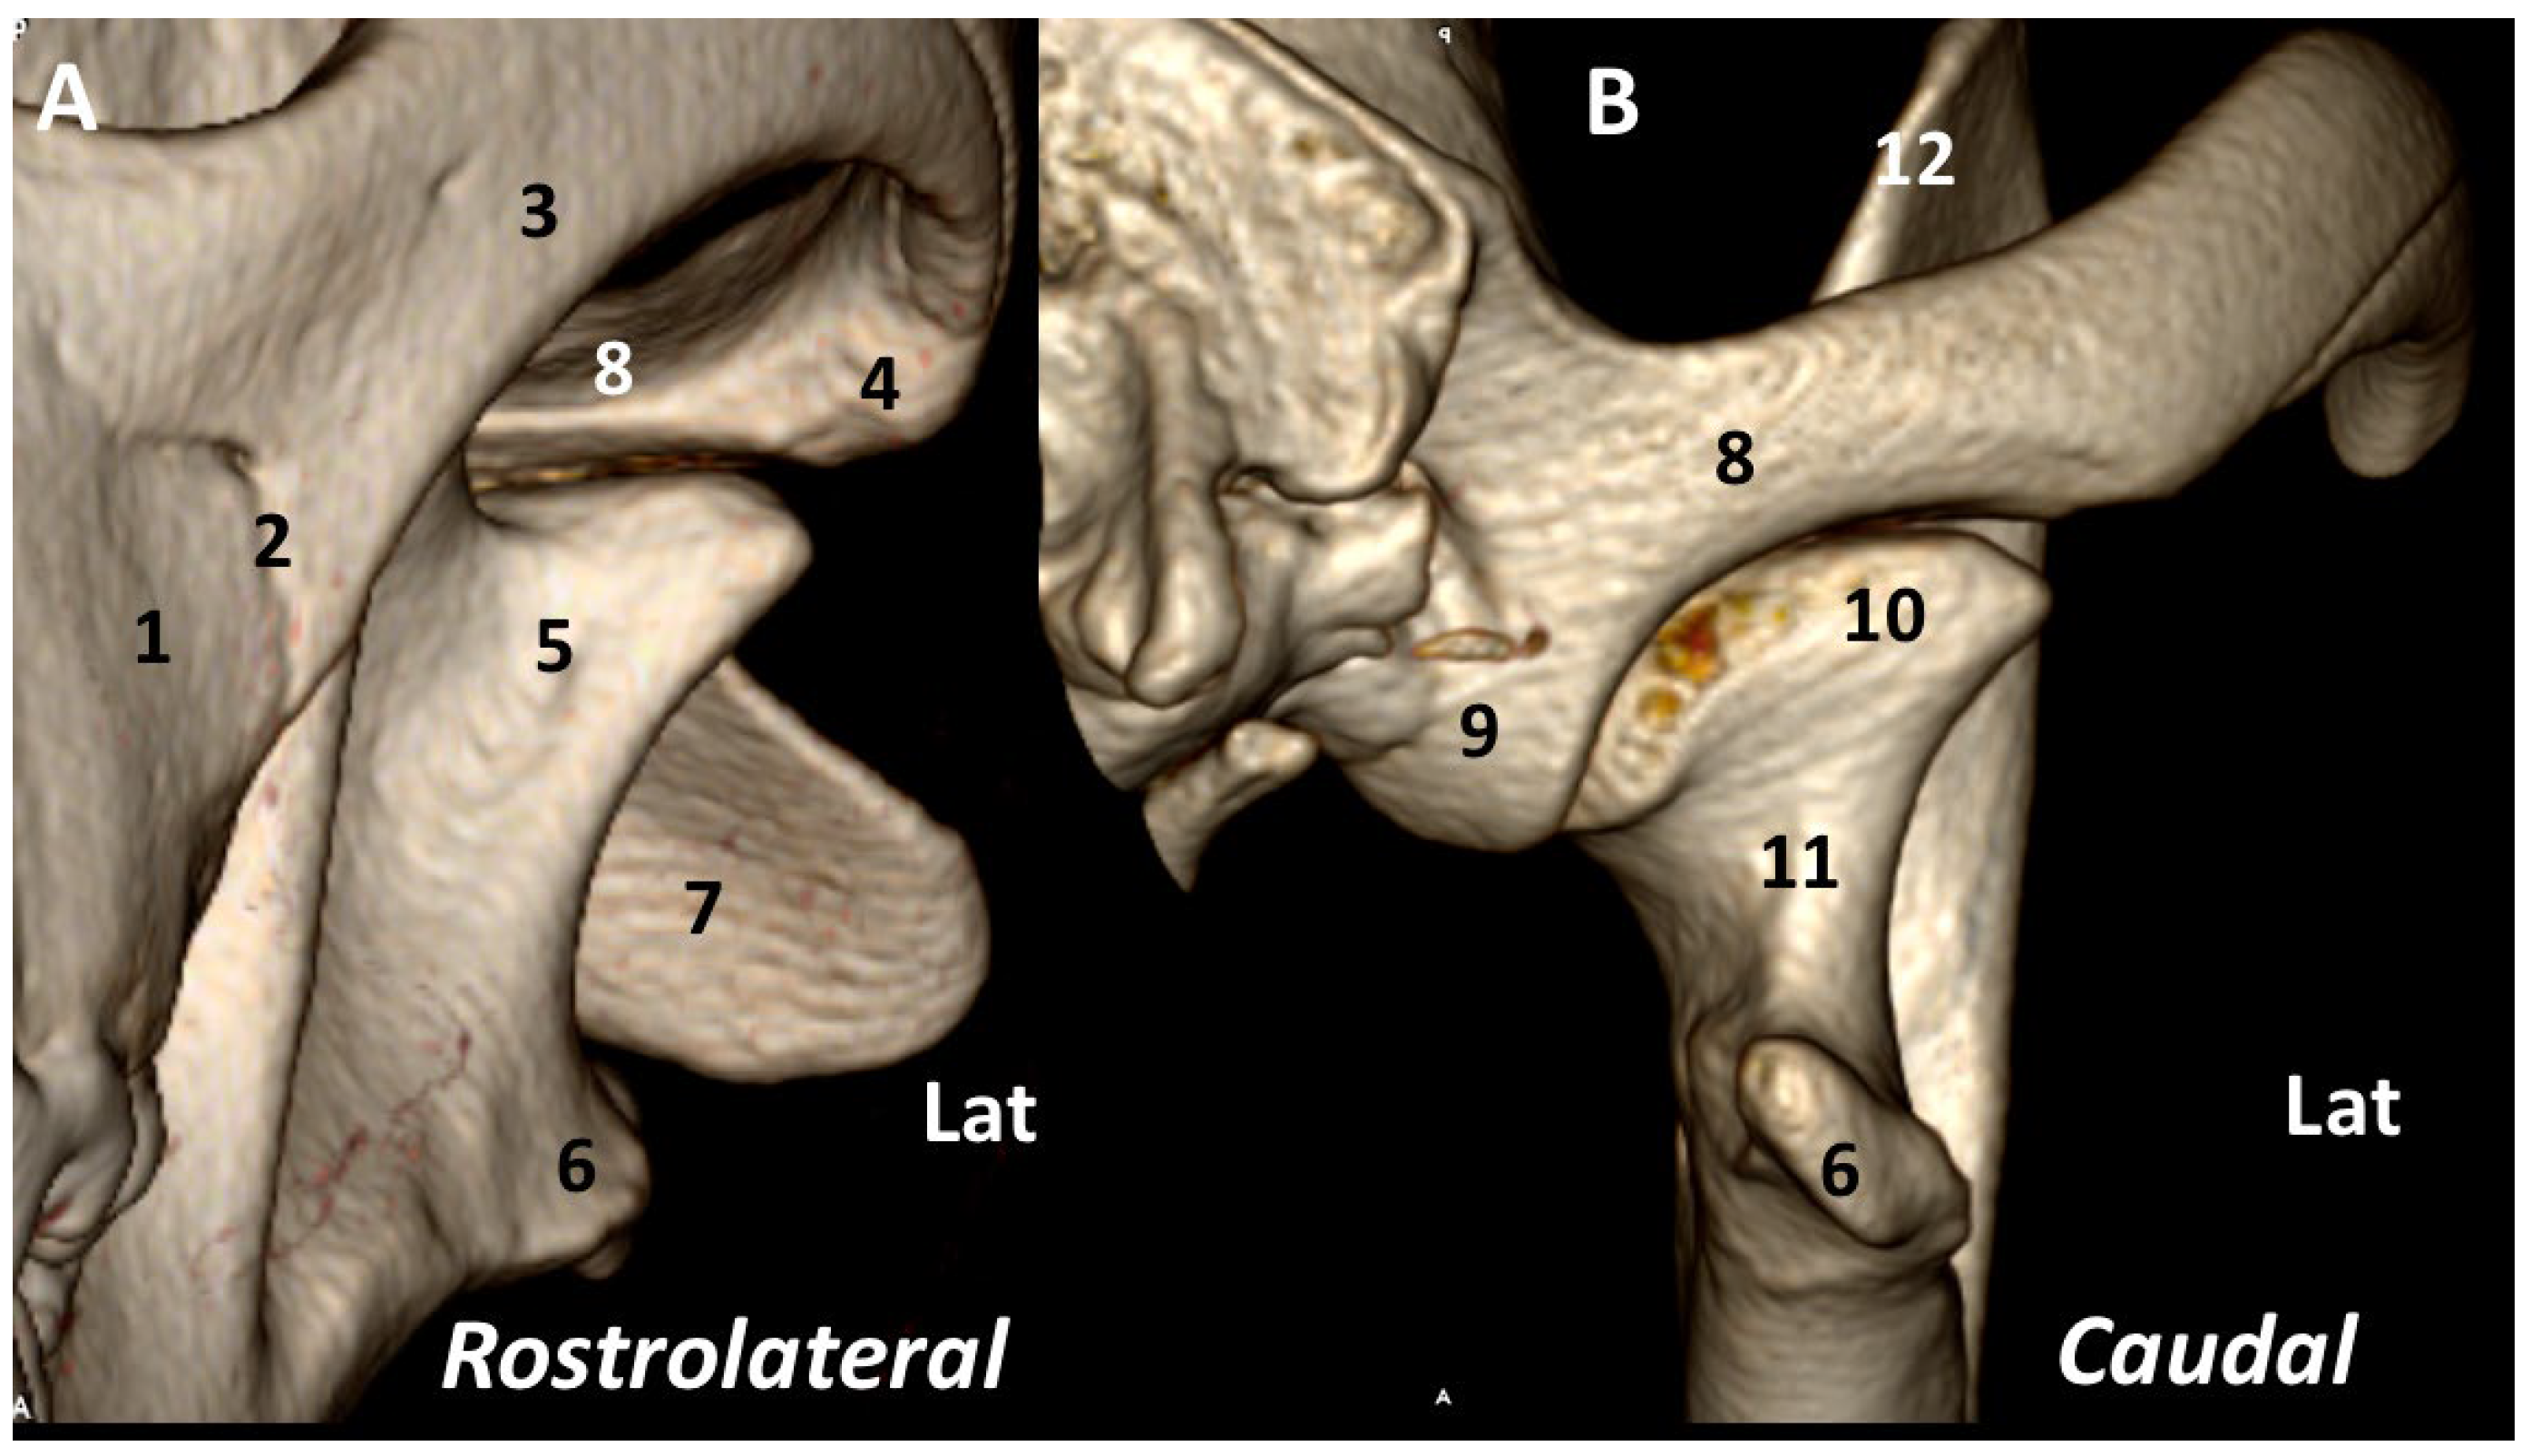

3.1. A Detailed Description of the Bone Anatomy of TMJ Using 3DVR Images